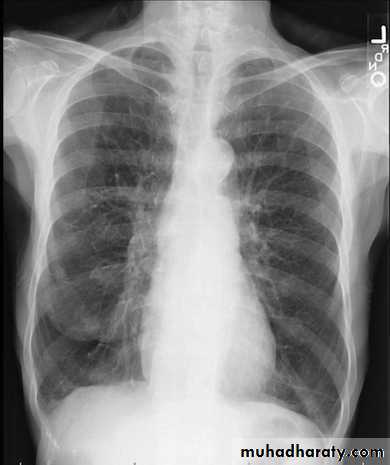

Unilateral obstructive emphysemaunilateral emphysema or atelectasis are the most common findings; only uncommonly will a radio-opaque foreign body be demonstrated ,Aspirated foreign bodies have a predominance for the right tracheo bronchial tree.